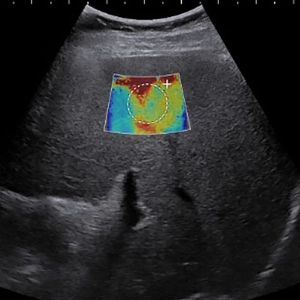

سیستم  Liver Fibrosis Assessment

توانبخشی

توسط admin - ۱۳۹۷/۰۲/۱۷ 0 نظرات